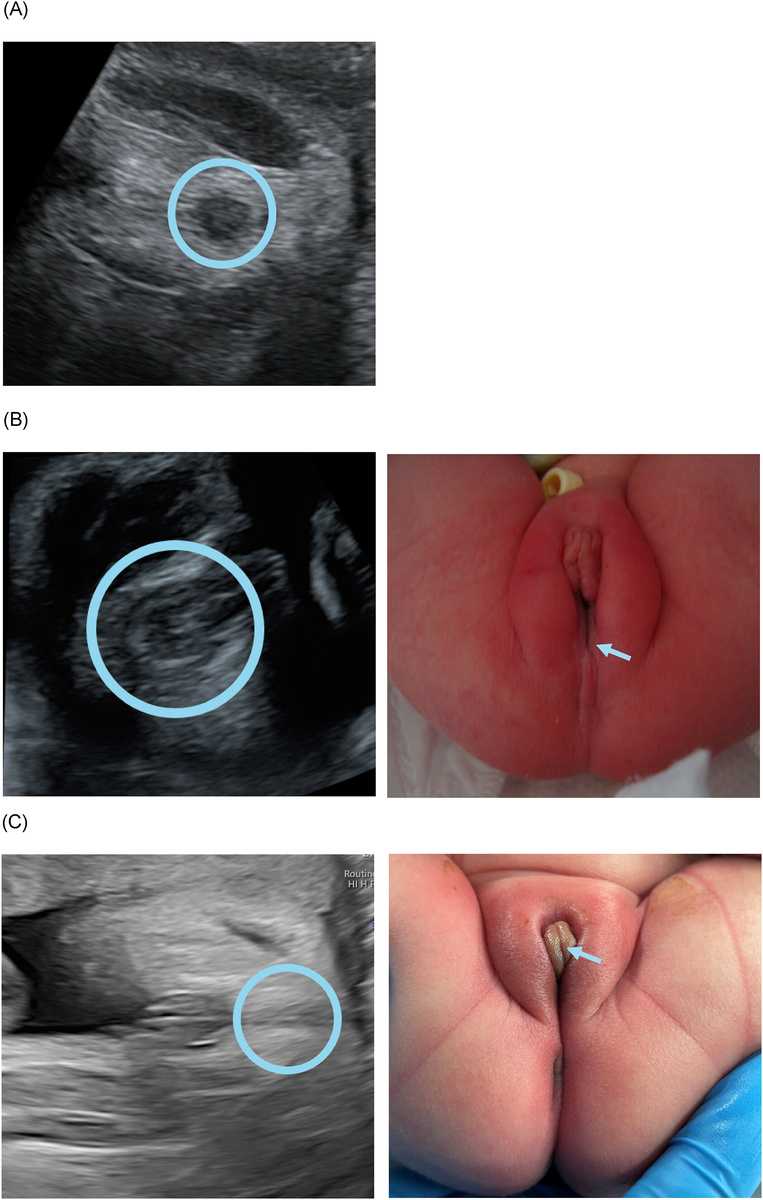

Нормальный, аномальный и отсутствующий "признак мишени" с соответствующим постнатальным изображением.

(A) Изображение нормального целевого признака.                                                                             (B) Изображение аномального по форме и смещенного кпереди признака мишени, а также соответствующее постнатальное изображение отсутствующего ануса в ожидаемом положении, но с фистулой, которая заканчивается в преддверии (прямокишечно-преддвериевый свищ, синяя стрелка).

(C) Изображение отсутствующего целевого признака вместе с соответствующим постнатальным изображением порока развития клоаки, при котором мочевыводящие пути, влагалище и прямая кишка имеют один общий канал (синяя стрелка).

Нормальный, аномальный и отсутствующий "признак мишени" с соответствующим постнатальным изображением. (A) Изображение нормального целевого признака. (B) Изображение аномального по форме и смещенного кпереди признака мишени, а также соответствующее постнатальное изображение отсутствующего ануса в ожидаемом положении, но с фистулой, которая заканчивается в преддверии (прямокишечно-преддвериевый свищ, синяя стрелка). (C) Изображение отсутствующего целевого признака вместе с соответствующим постнатальным изображением порока развития клоаки, при котором мочевыводящие пути, влагалище и прямая кишка имеют один общий канал (синяя стрелка).